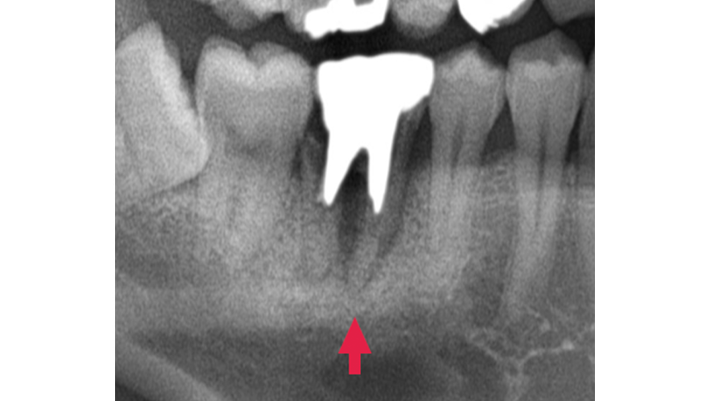

初診時には、深い歯周ポケットや垂直性骨欠損、歯の動揺が認められました。まずは歯周基本治療を行い炎症の改善を図りましたが、歯周ポケットや骨の欠損が残存していました。このままでは歯の保存が難しくなる可能性があったため、歯を残すことを目的として歯周組織再生療法を選択しました。

| 主訴 | 歯周病が進行し、抜歯と言われた。 |

|---|---|

| 治療期間 | 1回 |

| 治療費 | ¥77,000 |

| 治療内容 | 歯周基本治療をし、改善が認められなかったため歯周外科手術を行い、歯周組織の再生を目的とした再生療法を行いました。 |

| 治療のリスク | 腫れ・痛み・感染などの可能性があります。 |